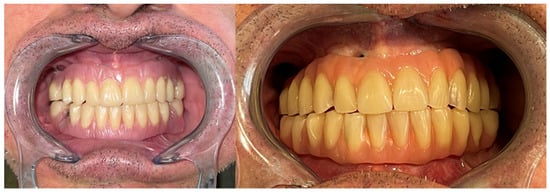

Immediate reconstruction of the defect was performed with an inferiorly based FAMM flap (Figure 3 and Figure 4) and immediate placement of 12 dental implants, 6 in the mandible and 6 in the maxilla (Figure 5). There were no postoperative complications, and the patient received postoperative radiotherapy (60 Gy). Eight months later, prosthetic rehabilitation of the dental implants was performed, and the aesthetic and functional evaluations were accomplished.

Mouth opening was evaluated as normal and lingual mobility as excellent for tip elevation, lingual protrusion, and lateral movements (Figure 6 and Figure 7). The patient was rehabilitated with two implant-supported prostheses (Figure 8, Figure 9 and Figure 10). Their speech articulation was evaluated as normal and the patient reported a normal diet without restrictions. From the aesthetic point of view, the patient reported an excellent result (Figure 11).

Figure 8. Metal framework evaluated intraorally for functional rehabilitation with a fixed implant-supported prosthesis. FAMM flap for right tongue and floor of the mouth reconstruction.

Jcm 10 03625 g008

Figure 9. Prosthetic rehabilitation with a fixed implant-supported prosthesis and final occlusion.

Jcm 10 03625 g009